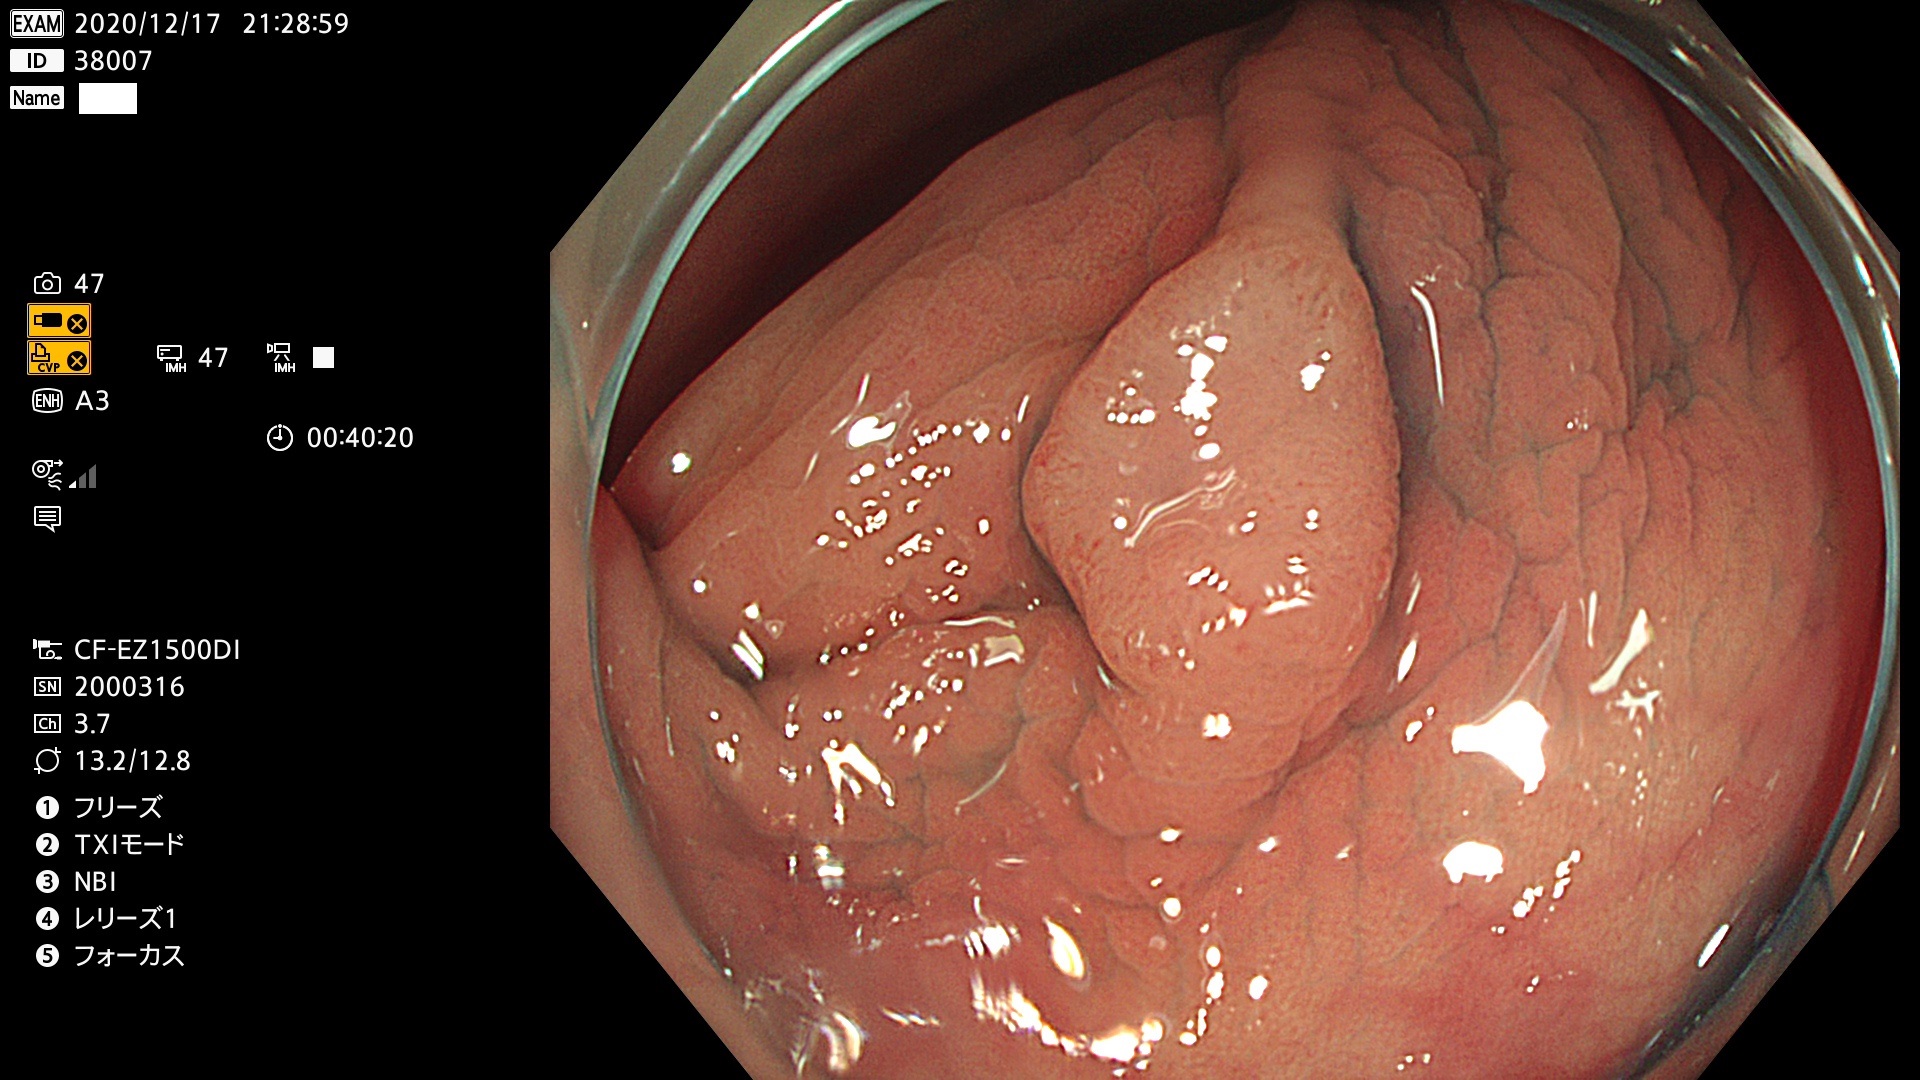

38001 38002 38003 38004 38006(SSAPのみ) 38007 38008 38009 38010 38012 38013 38014 38016 38018 38020 38021 38025 38026 38029 38032 38033 38034 38035 38036 38037(SSAPのみ) 38039 38043 38044 38048 38049 38050 38052 38055 38056 38057 38058 38059 38064(SSAPのみ) 38065 38068 38069 38070 38071 38072 38074 38075 38076 38078 38079 38080 38082 38083 38084 38085(SSAPのみ) 38086 38087 38088 38089 38090 38091 38092 38093 38094 38097 38098 38099

発見困難で危険性の高い平坦型病変(上記100名より抽出)